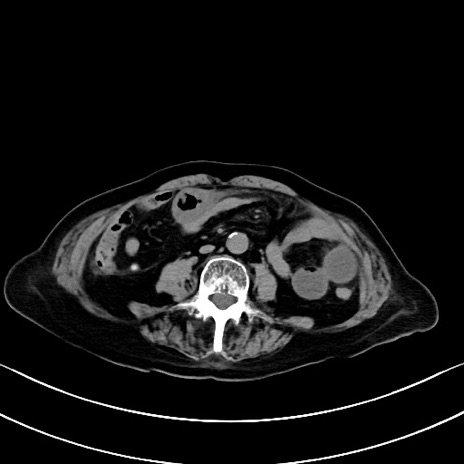

症例40(横断像)他院1日前

横断像